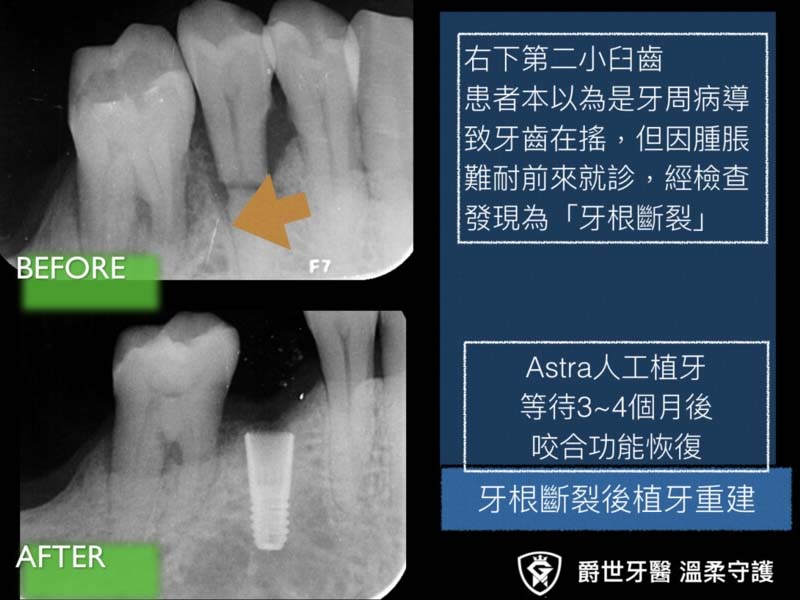

牙根斷裂,植牙咬合重建